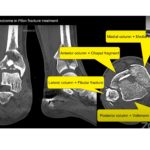

How to improve Outcome in Pilon fracture treatment?

Courtesy: Squadron Leader Dr Pongpol Petchkum, MD Bhumibol Adulyadej Hospital, Bangkok